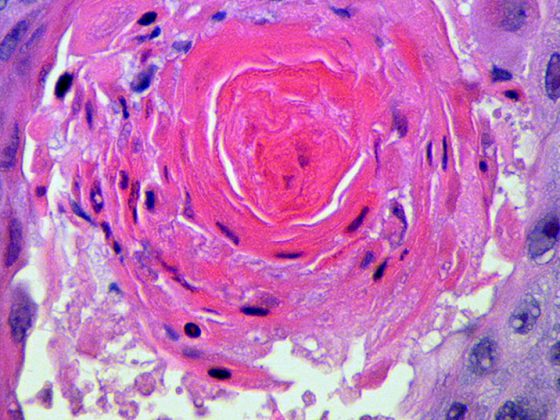

• Seltene Vaskulitiden – Polyarteriitis Nodosa (PAN)